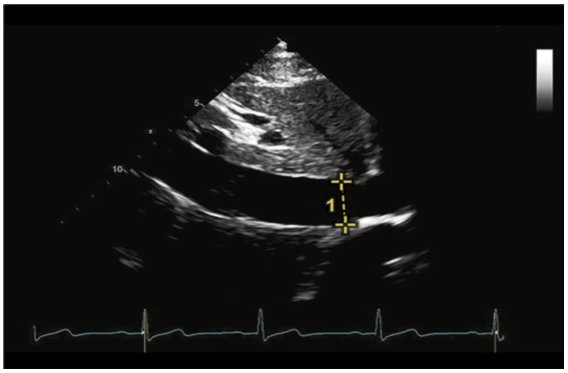

循环系统的构建需要有一定的容量基础,称为前负荷;有泵血能力的心脏,是形成循环系统的原动力;外周血管的阻力,维持脏器灌的压力,此处被称为后负荷。临床中,我们常规通过中心静脉压(CVP)、舒张末期全心四腔容积指数(GEDI)、肺动脉楔压(PAWP)等静态指标来精准评估患者的前负荷情况,通过脉压变异率(PPV)、每搏量变异率(SVV)等动态指标来评估患者可能对容量的反应性。在重症超声中,我们通过监测以下指标来评价患者体循环前负荷的状态。(1)IVC的直径:在剑突下四腔心切面,移、转、摇探头,找到IVC到右心房入口的位置,测量IVC距右心房2 cm处的宽度,将该处直径作为IVC的宽度。测量示意图如图5所示。

图5 下腔静脉的测量